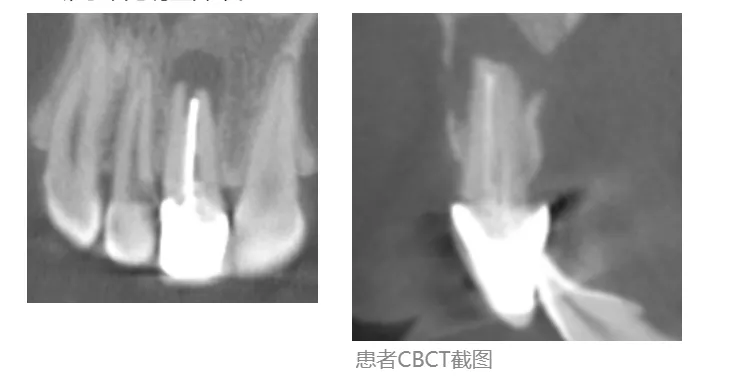

·      影像学检查

·      11牙根管内高密度影,根尖周低密度影;

·      11根尖炎症波及唇舌侧骨板,唇侧骨板根方穿通,舌侧骨板基底处穿通;

·      邻牙未见明显异常。